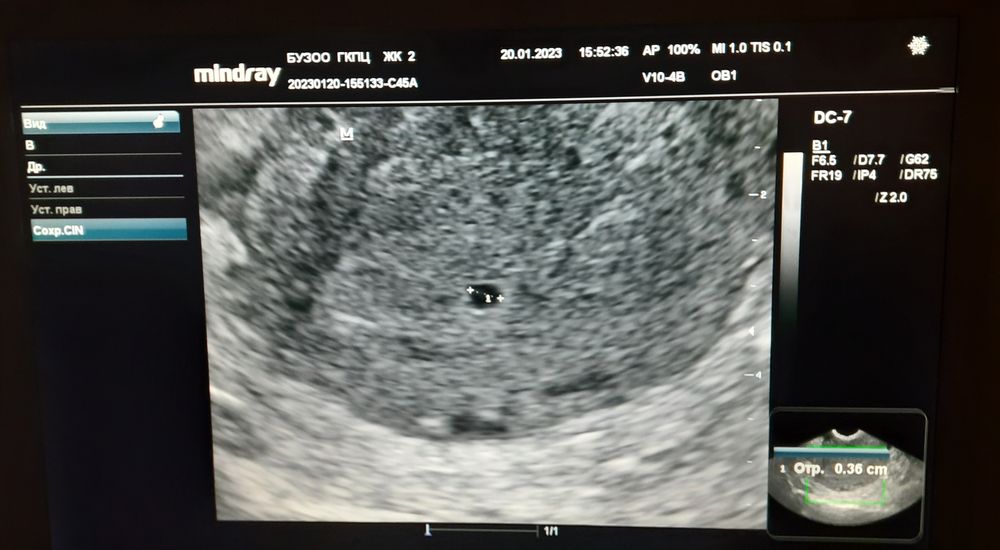

Страхи, переживания и немножечко нытьяПойду завтра опять сдавать ХГЧ наверно. У кого на сроке по мес. 5 нед. и 3 дня ПЯ было всего 3.6 (ну или ~4) как закончилась беременность?

3.6-4 мм это 5 недель и 1 день. Совершенно некритично. Даде если вы точно знаете овуляцию , оплодотворение могло быть под конец "жизни" яйцеклетки, прикрепится не на 5, а на 7 день например. А уж если не знаете 100% день, в обще не надо в голову это брать.

В эту беременность в 5.1 и по мес. Свд 3.6. было.